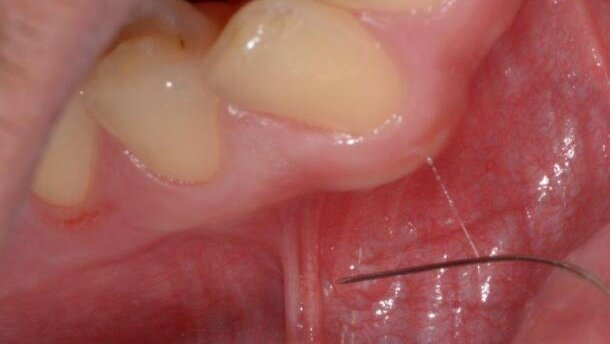

Podobny efekt uzyskamy, gdy mocno napniemy błonę śluzową, np. w miejscu wędzidła policzka (Ryc. 4). Wówczas również uzyskamy efekt anemizacji, a dodatkowo ewentualne uczucie ukłucia będzie maskowane przez tolerowane przez pacjenta uczucie naciągania policzka.